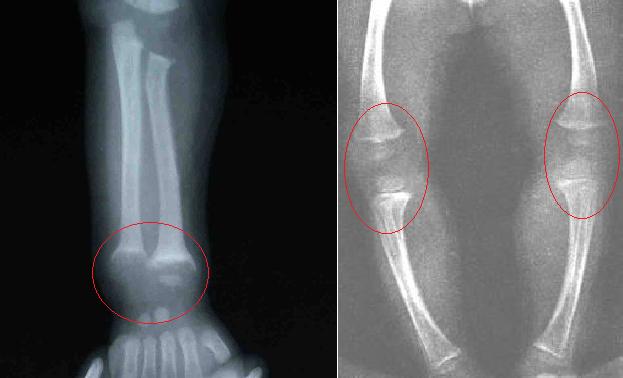

4、O形腿或X形腿

因为骨骼软化,婴儿爬行时可发生上肢弯曲,站立行走后则发生下肢弯曲。

另外,长骨骨骺端肥大,尤其是腕部、踝部,形成“手足镯”。

3、X射线检查

长骨发育较快,症状较明显,尤其是尺桡骨近腕关节处和胫腓骨近膝关节处最为明显。